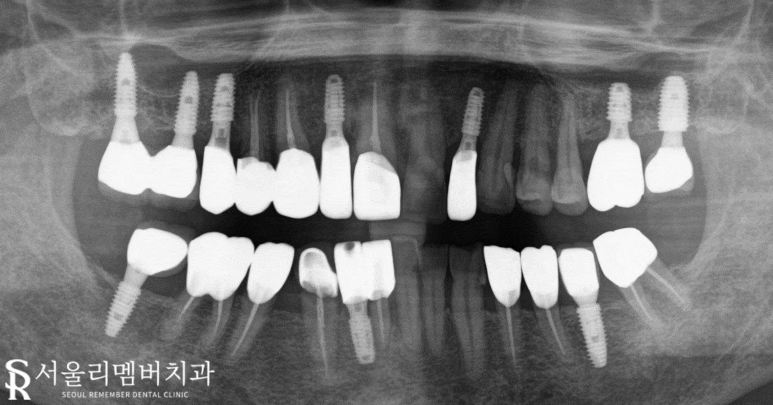

치료 종료 후 사진인데요,

엑스레이에서도

네비개이션 임플란트로 계획된 대로

올바른 위치에 잘 식립이 된 것이

확인되네요 :)